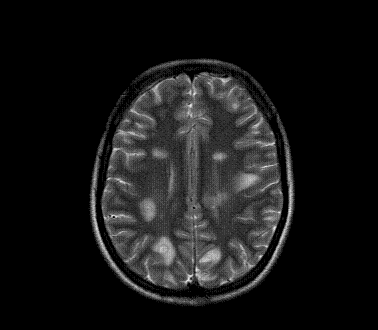

以下是引用xly在2009-5-20 11:38:00的发言:[br]大脑、小脑及脑干多发结节状及环状稍长t1、长t2异常信号影,部份病灶中心见稍短t1、短t2信号,病灶边缘光滑、边界清楚,灶周环状水肿,dwi为低信号,增强扫描上述病灶均匀强化,部份病灶中心无强化,脑膜小结节异常强化,考虑脑膜脑结核可能性大。胸片如何?ppd如何?期待结果。